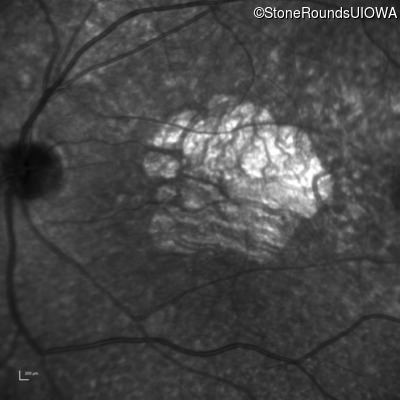

Age at visit: 30 years

This 30 year old man first noticed poor vision in dim light when he was five years old. His visual acuity began to fall in his early 20's.